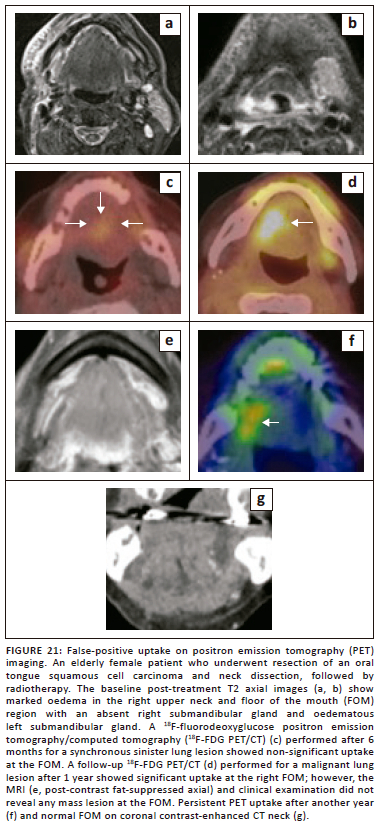

MR imaging can pose a significant challenge in the differentiation of recurrent or residual disease from post-treatment changes. Although 18F-FDG PET/CT has a very high negative predictive value for excluding recurrent disease in comparison to CT and MRI (Figure 19 and Figure 20), PET imaging also has its own limitations, including the possibility of false-positive results from post-treatment changes and physiological causes,5,29 as illustrated in Figure 21.